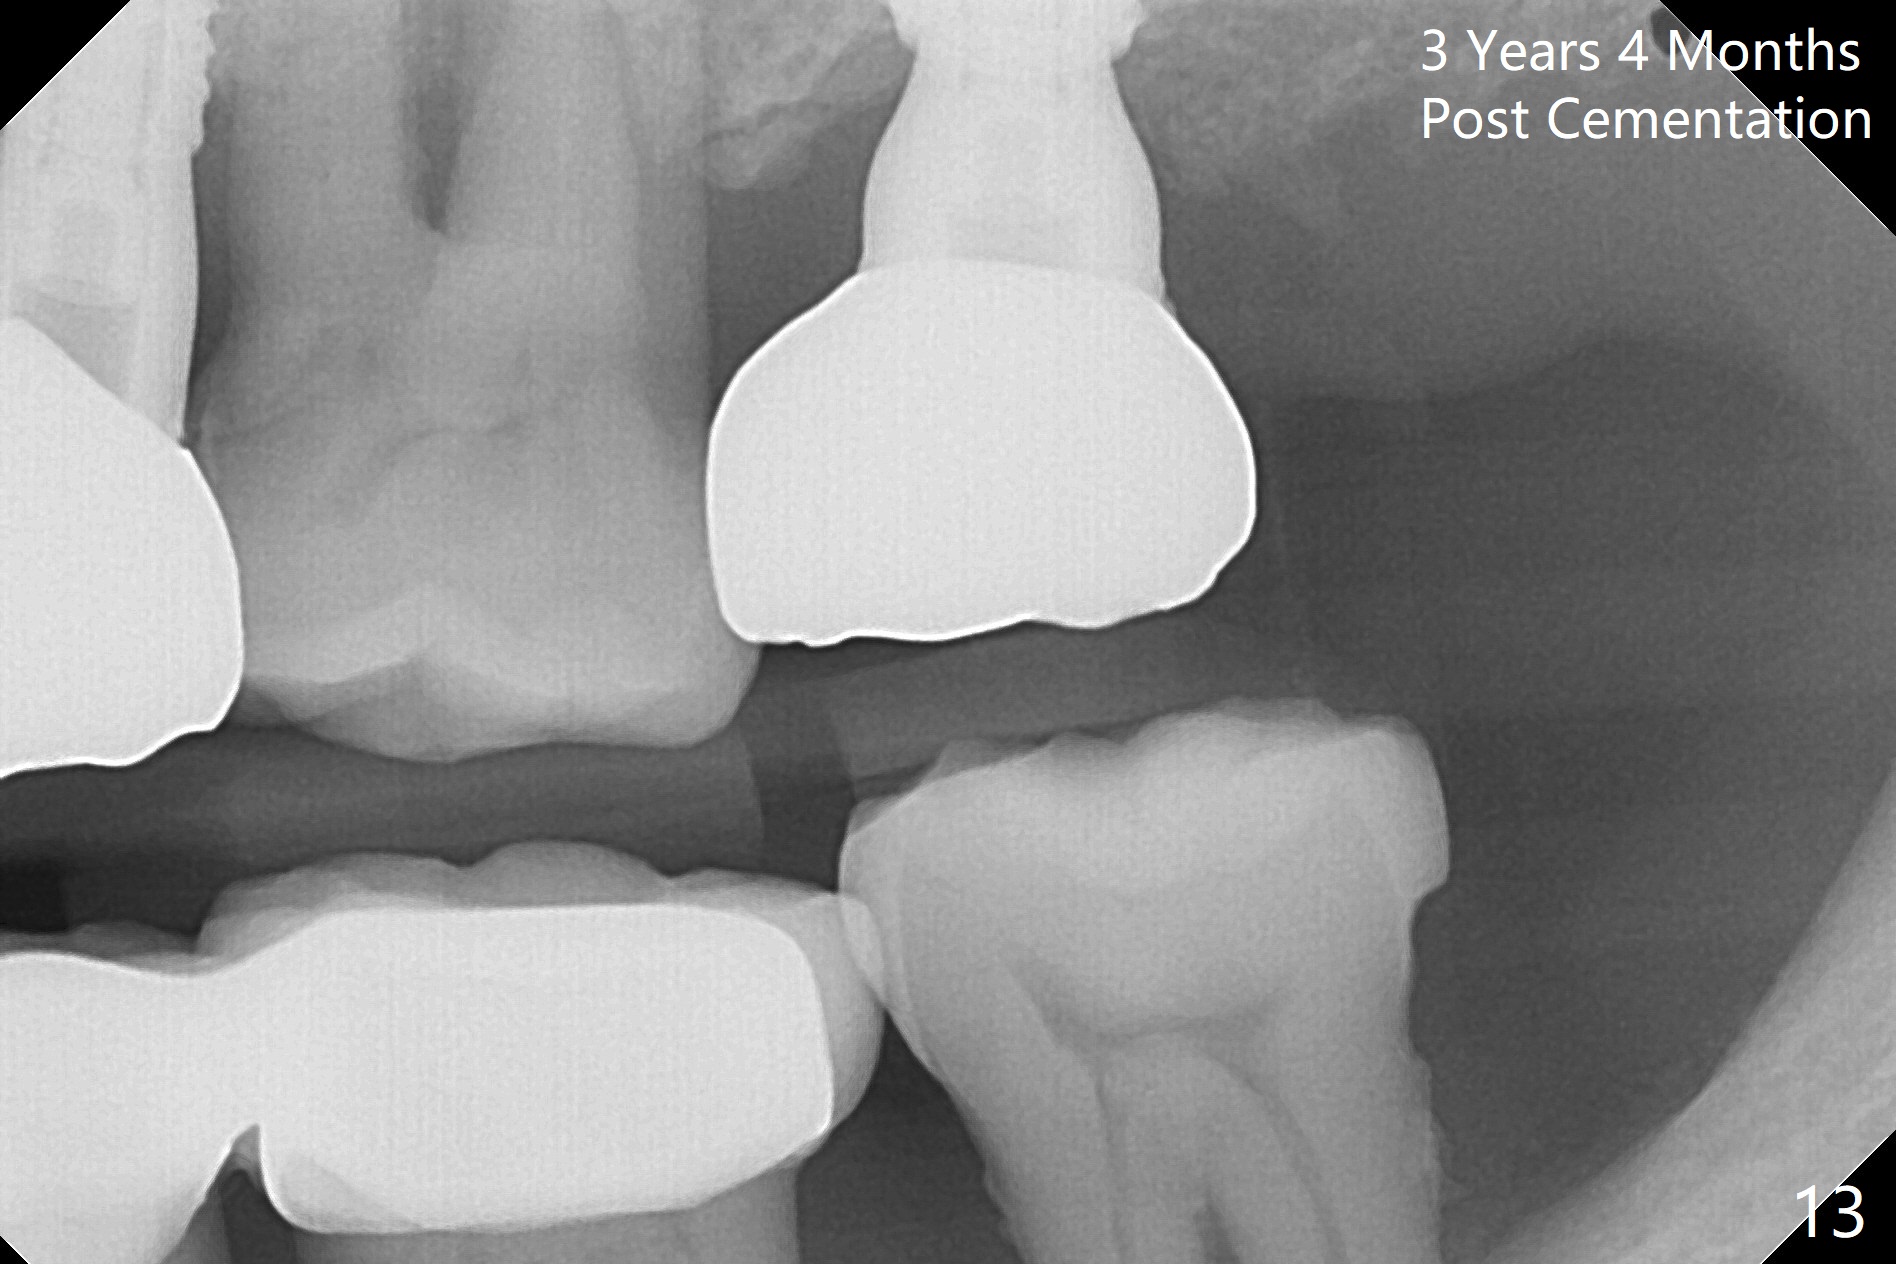

Initial osteotomy depth is 18 mm (Fig.1 green line) with 9 mm in the native bone (red line).  The bone density feels to be low.  There is at least 2 more mm bone apically (pink line).  The depth is increased by 2 mm so that when a 3.8x15 mm implant is placed, there is 10-11 mm implant/bone contact (Fig.2 red line).  There is large bony defect (Fig.3 *), which is bone grafted (Fig.4 *).  Finally a longer abutment is placed (4.5x5.5(5) in Fig.4 vs. 4.5x4(5) in Fig.2,3).  The 5 mm cuff does not look too long buccally (Fig.5) or palatally (Fig.6).   To prevent postop buccal gingival overgrowth (2), the buccal margin of an immediate provisional is subgingival (Fig.7-9 *).  Bone density between #13 and 14 appears to increase 3 months postop (Fig.10).  The implant seems to be equi-crestal (Fig.11 ^).  There seems to be more bone growth (i.e., decreasing gap) 6 months postop (Fig.12).  Impression is taken.  A crown is delivered nearly 7 months postop (08/07/2017).   While there is minimal bone loss at #13 and 15 three years and 4 months post cementation, the tooth #14 and 18 are mobile (Fig.13,14).